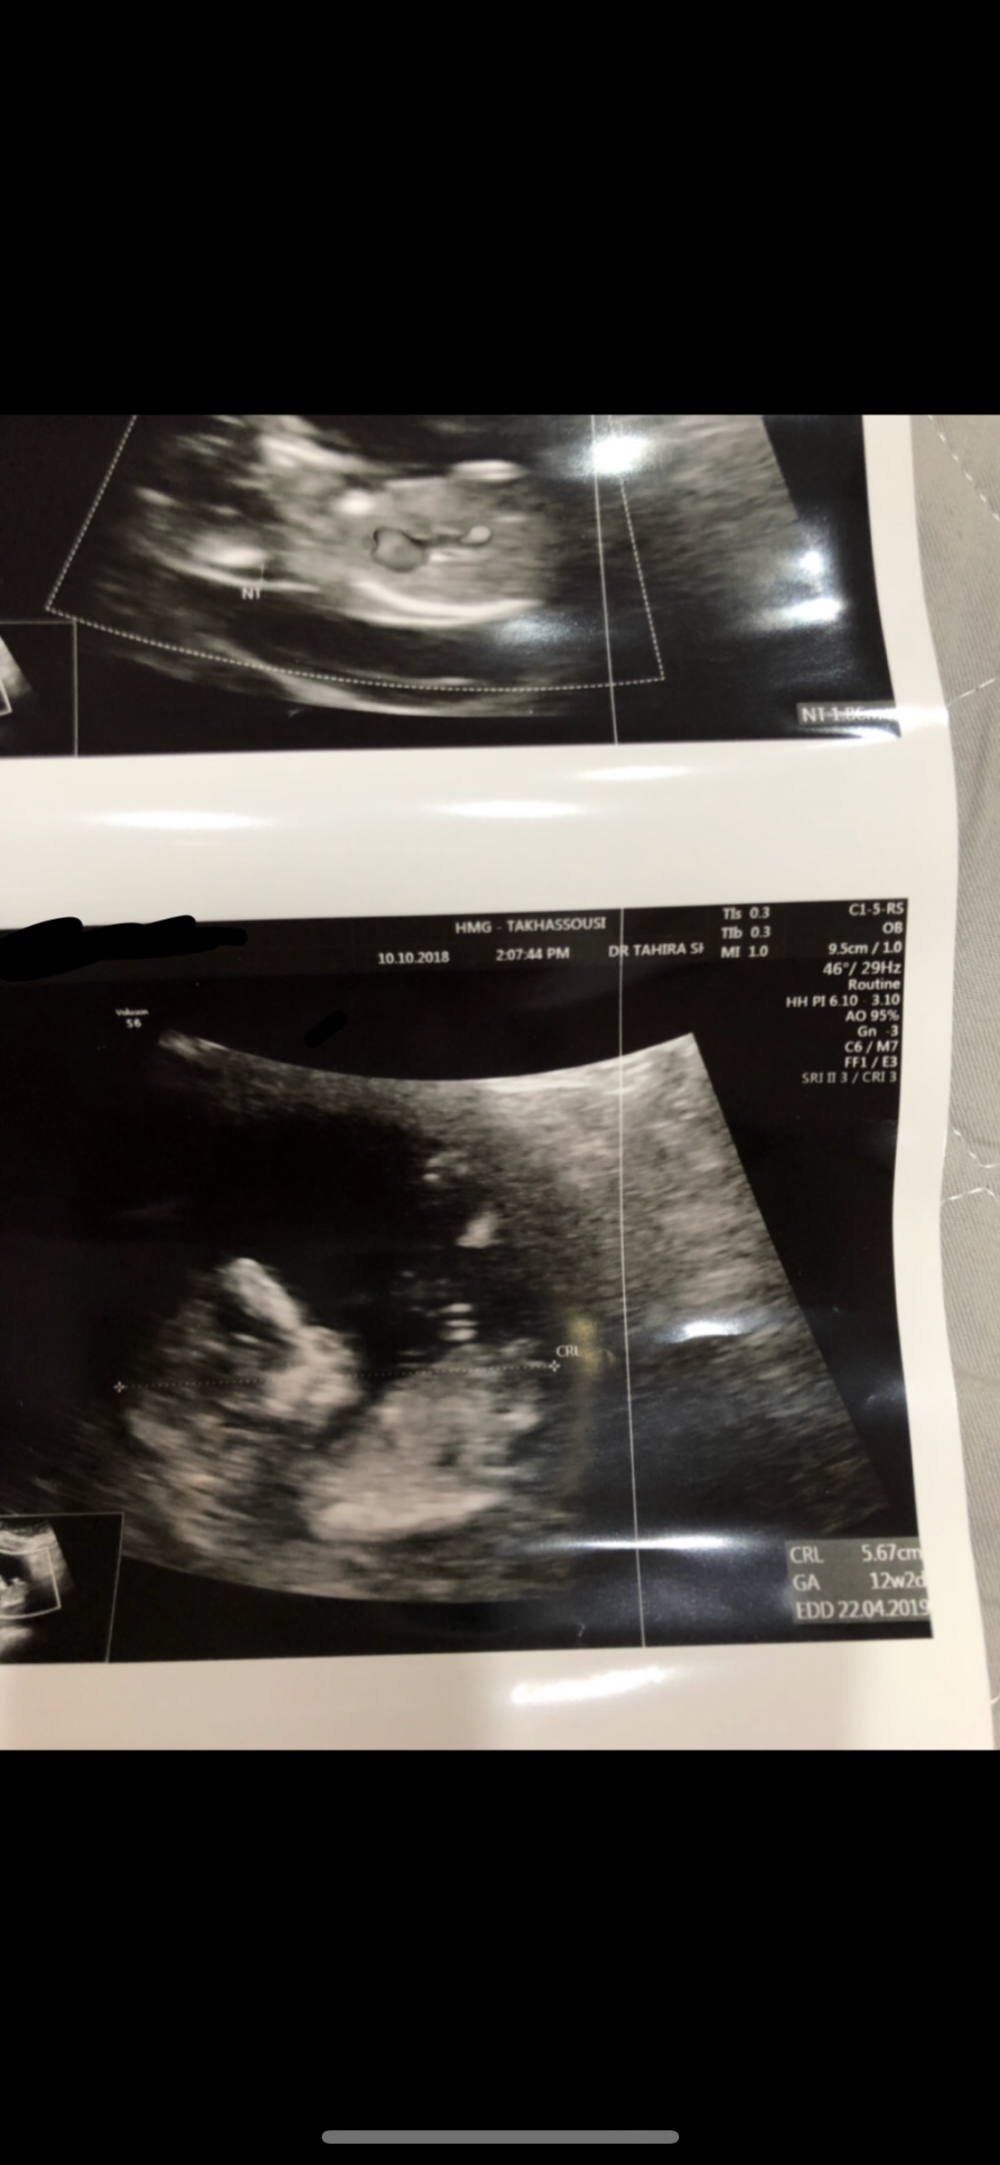

ماشاء الله تبارك الله

واضح انه جاب نتيجه😬😬😬

وهذي صورة ثانيه 🌚